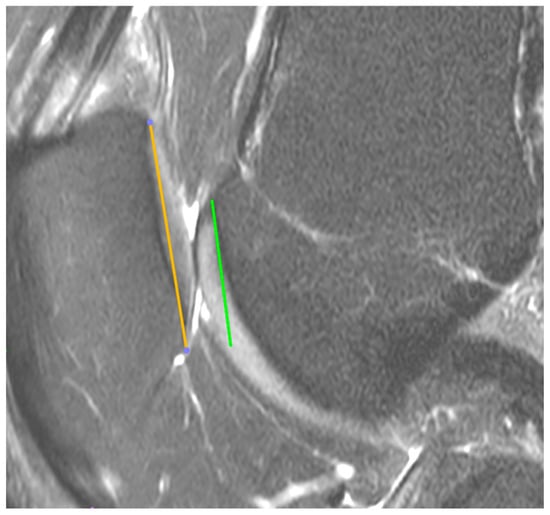

2.2. MRI Analysis

| SA | Sulcus angle |

| PTA | patellar tilt angle |